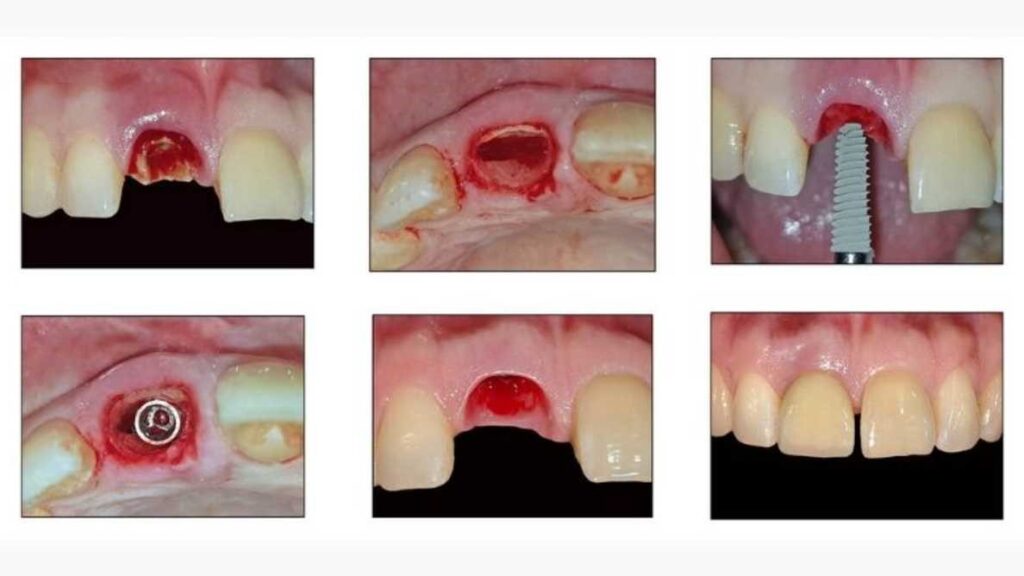

Immediate Implant Placement

Immediate implant placement is an advanced procedure where a dental implant is placed immediately after tooth extraction during the same visit. This modern treatment helps restore your smile quickly while preserving the natural bone and gum structure.

Benefits of Immediate Implant Placement

- Faster smile restoration

- Reduced treatment time

- Preserves jawbone and gums

- Minimally invasive procedure

- Fewer dental visits

- Natural-looking results

- Improved comfort and confidence

- Support faster recovery in suitable cases

- Using advanced digital technology and precision planning, immediate implants provide faster healing, improved aesthetics, and long-lasting results.